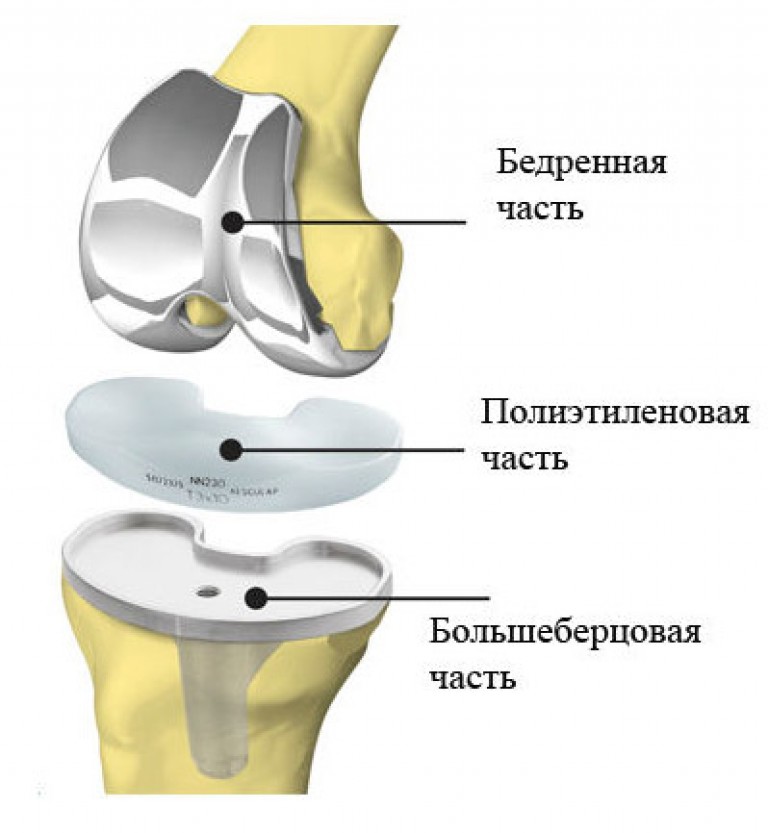

Примеры протезов коленных суставов Zimmer